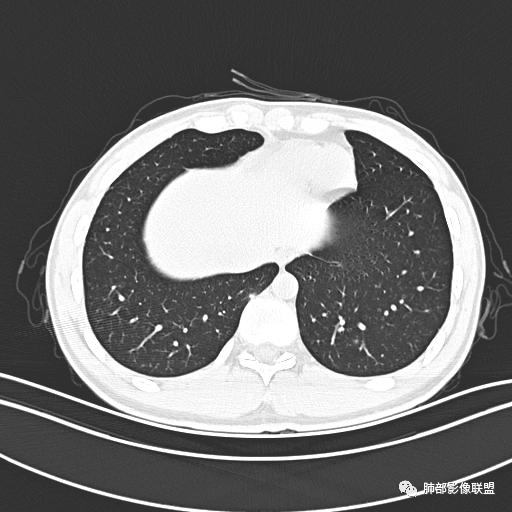

【每日晨读】年轻男性,发热+皮疹+肺内点晕

主  诉:发热、全身皮疹2天。

现病史:患者源于2天前受凉后出现发热,最高体温为38.5℃,且颜面部出现少量皮疹,无鼻塞、流涕、咳嗽、咳痰,未在意而未作特殊处理,次日全身皮疹逐渐增多至全身,伴轻度瘙痒,在当地卫生所给予抗病毒、抗感染治疗(具体用药不详)体温有所下降,但皮疹无明显消退,无腹痛、头痛,食欲无明显减退,为进一步诊治,遂于今日急来我院求治,患者目前精神尚可,体力正常,食欲正常,睡眠正常,体重无明显变化,大便正常,排尿正常。

小强:青年,发热,皮疹;双肺散在结节,周围磨玻璃,点晕征,疱疹病毒感染,鉴别荚膜组织胞浆菌,结核。 大雄:青年,急性起病,发热伴全身皮疹2天,抗病毒治疗体温有下降。双肺随机分布大小不等类圆结节,“点晕征”。考虑水痘-疱疹病毒(VZV)血播询问接触史,查体皮疹分布以及形态基本可诊断。 王开金江津中心医院呼吸科:青年男性,起病急,病程短,以发热,皮疹为首发症状,感染指标以单核细胞升高为主,胸部ct双肺多发结界,周围有晕,点晕表现,随机分布,同意於老师意见,水痘疱疹病毒血流感染累及肺。 王秀仙:双肺多发大小不等结节,周围有晕,边缘模糊,呈点晕征表现。青年,急性起病,发热伴全身皮疹2天,抗病毒治疗体温有下降。考虑疱疹病毒。鉴别荚膜组织胞浆菌。 傅昌瑜:19岁男性,发热、全身皮疹2天,单核细胞增高,双肺多发结节,结节边缘见边界不清磨玻璃影。点晕征+发热、全身皮疹+单核细胞增高——考虑水痘-带状疱疹病毒肺炎。 一切∮随缘:年轻男性,发热,皮疹两天,实验室,CRP,PCT增高,影像:双肺多发散在磨玻璃结节,边界欠清,大小不等,呈点晕征改变,以血管束周围分布为主,局部血管束略增粗,其它无明显改变,考虑:1:病毒性肺炎(水痘疱疹病毒?不知道皮肤有无改变)2:真菌(组织胞浆菌,血管侵袭性肺曲霉)3:GPA4:寄生虫(实验室没有看到嗜酸细胞增高) 赵山河:双肺散在结节,周围有晕,边缘模糊,呈点晕征表现。青年,急性起病,发热伴全身皮疹2天,抗病毒治疗体温有下降。考虑水痘—疱疹病毒感染。洪桥爱:青年男性,发热、皮疹2天,伴瘙痒,皮疹于面部首发,之后进展至全身,虽然没有对皮疹进行描述,但是从出疹时间及皮疹进展情况,伴瘙痒,应该就是个水痘患者;CT提示双肺随机分布结节影,部分结节伴有边界不清晕征,考虑水痘血播肺。 刘强:年轻男性,急性起病,皮疹,发热,抗感染治疗体温下降,说明有效。影像表现为散在点晕征,感染类疾病谱(疱疹病毒,真菌,结核),结合年龄,皮肤皮疹,考虑水痘-疱疹病毒性肺炎。 小兜:男性,19岁,发热皮疹两天,颜面部至全身,CRP,降钙素及单核增高。CT示双肺散在小结节,周围伴磨玻璃影,点晕征,考虑为水痘-带状疱疹病毒(varicella-zoster virus,VZV)肺炎 必有路:青年,皮疹+发热+“点晕征”→水痘-疱疹病毒(VZV) 许慧良:青年男性患者,发热、皮疹2天,体温最高38.5℃,第3天皮疹扩展至全身,伴瘙痒,胸部CT:双肺多发随机分布的小结节,结节周边见边界模糊的晕征,考虑水痘病毒感染流心明智:男,19,急性起病,发热伴全身皮疹2天。出疹顺序头→全身,抗病毒有效。胸部CT:两肺多发大小不等类圆形实性小结节影,随机分布,结节周围环绕GGO,边界模糊,呈点晕征。出疹特点是关键,未提示。考虑:血播病毒性肺炎,水痘-疱疹病毒?麻疹?鉴别荚膜组织胞浆菌、TB、血管炎、寄生虫等。 浪迹天涯:病灶多为5-10mm大小结节,结节周围可见磨玻璃样的晕环,常多发,可分布于肺内任何区域,考虑水痘—带状疱疹病肺炎如果短时间内有新的一个区域浸润,更加能说明,